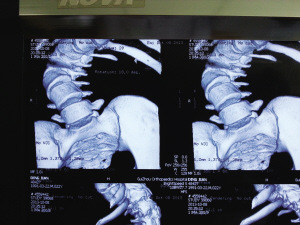

術(shù)前,小健脊柱側(cè)彎嚴(yán)重。

術(shù)后“長高”了12公分。

今年1月,小健感覺身體不適,便在親友陪同下來到省骨科醫(yī)院。經(jīng)檢查,醫(yī)生發(fā)現(xiàn)小健脊柱后凸彎近150度,側(cè)凸近130度,肺功能受損達(dá)30%。因小健已經(jīng)22歲,脊柱生長已經(jīng)停止,十分僵硬,錯(cuò)過了最佳治療期,只能做脊柱側(cè)彎矯正手術(shù),但該手術(shù)費(fèi)用高,難度大。

8個(gè)小時(shí)的手術(shù)中,小健共被植入19根金屬釘。手術(shù)成功后,小健背部包塊不見了,身高從156公分“躥”到168公分。昨日,出院后的小健來到醫(yī)院復(fù)查,恢復(fù)結(jié)果良好。